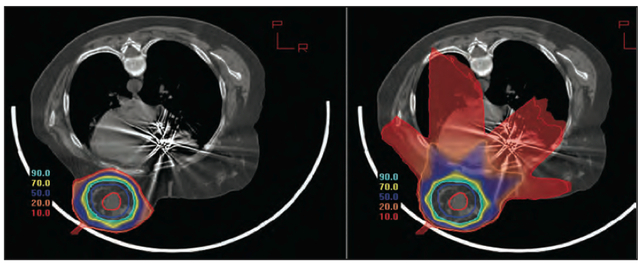

粒子放疗精准、副作用小,特色优势明显,目前重离子医院累计采用质子射线放疗乳腺癌患者345例,其中随访时间满6个月的患者244例,中位随访时间24个月,患者两年总生存率达100%,两年无瘤生存率达97%,随访仅观察到皮肤色素沉着等轻微副反应,未见常规光子放疗可能出现的对心脏的相关毒副反应。

重离子医院同时充分发挥与复旦大学附属肿瘤医院高度融合的优势,两院各学科专家团队正携手开展质子联合重离子治疗特殊分子亚型及对常规放疗不敏感的难治性乳腺癌(如三阴性乳腺癌、HER-2阳性乳腺癌等)的科研攻关,帮助此类患者获得长期生存并改善生活质量。